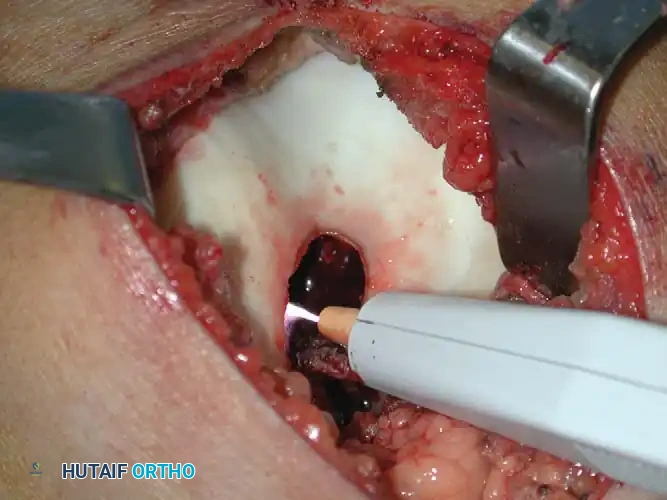

4. Mechanical and Thermal Adjuvants (Extended Curettage)

Once gross tumor is removed, the cavity undergoes extended curettage to eliminate microscopic disease residing in the cancellous bone trabeculae.

- High-Speed Burr: A high-speed motorized burr is used to aggressively abrade the walls of the cavity until normal, healthy bleeding cortical or cancellous bone is encountered.

- Thermal Coagulation: An Argon Beam Coagulator (ABC) or electrocautery is applied to the cavity walls. The argon beam provides a uniform depth of thermal necrosis (approximately 2-3 mm), effectively destroying residual microscopic tumor cells without compromising the structural integrity of the entire bone.

*Fig. 21-6E & F: (Left) Intraoperative photograph demonstrating the large cortical window and the cavity after gross curettage of the intercondylar notch lesion. (Right